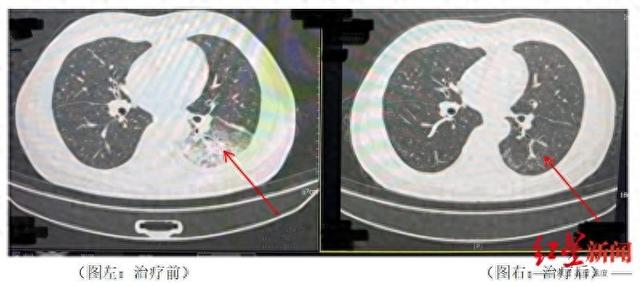

近日,成都气温逐步升高,市民李先生在开启尘封一年的空调后,竟意外患上了严重的军团菌肺炎,左肺接近“白”了一半。经过成都市第五人民医院感染性疾病科的诊断和治疗,李先生已康复出院。

李先生肺部治疗前与治疗后的对比

据悉,开启空调降温3天后,李先生出现了肌肉酸痛、头痛、发热和咳嗽等症状。起初,他以为是吹空调吹感冒了,于是自行服用感冒药,但病情并未好转,反而愈发严重。家人见状,立即将他送往成都市第五人民医院感染性疾病科。胸部CT显示李先生的左肺已出现大面积白色影像,几乎占据一半肺部。经过肺泡灌洗NGS检测,最终确认“罪魁祸首”是嗜肺军团菌。